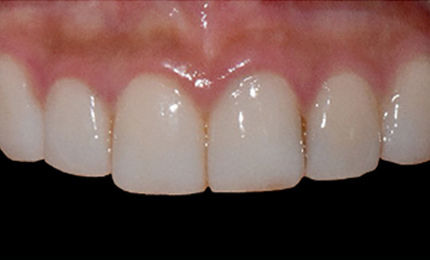

• 시술전

최소삭제 0.1mm - 0.2mm, 최대 0.3mm

시술 후